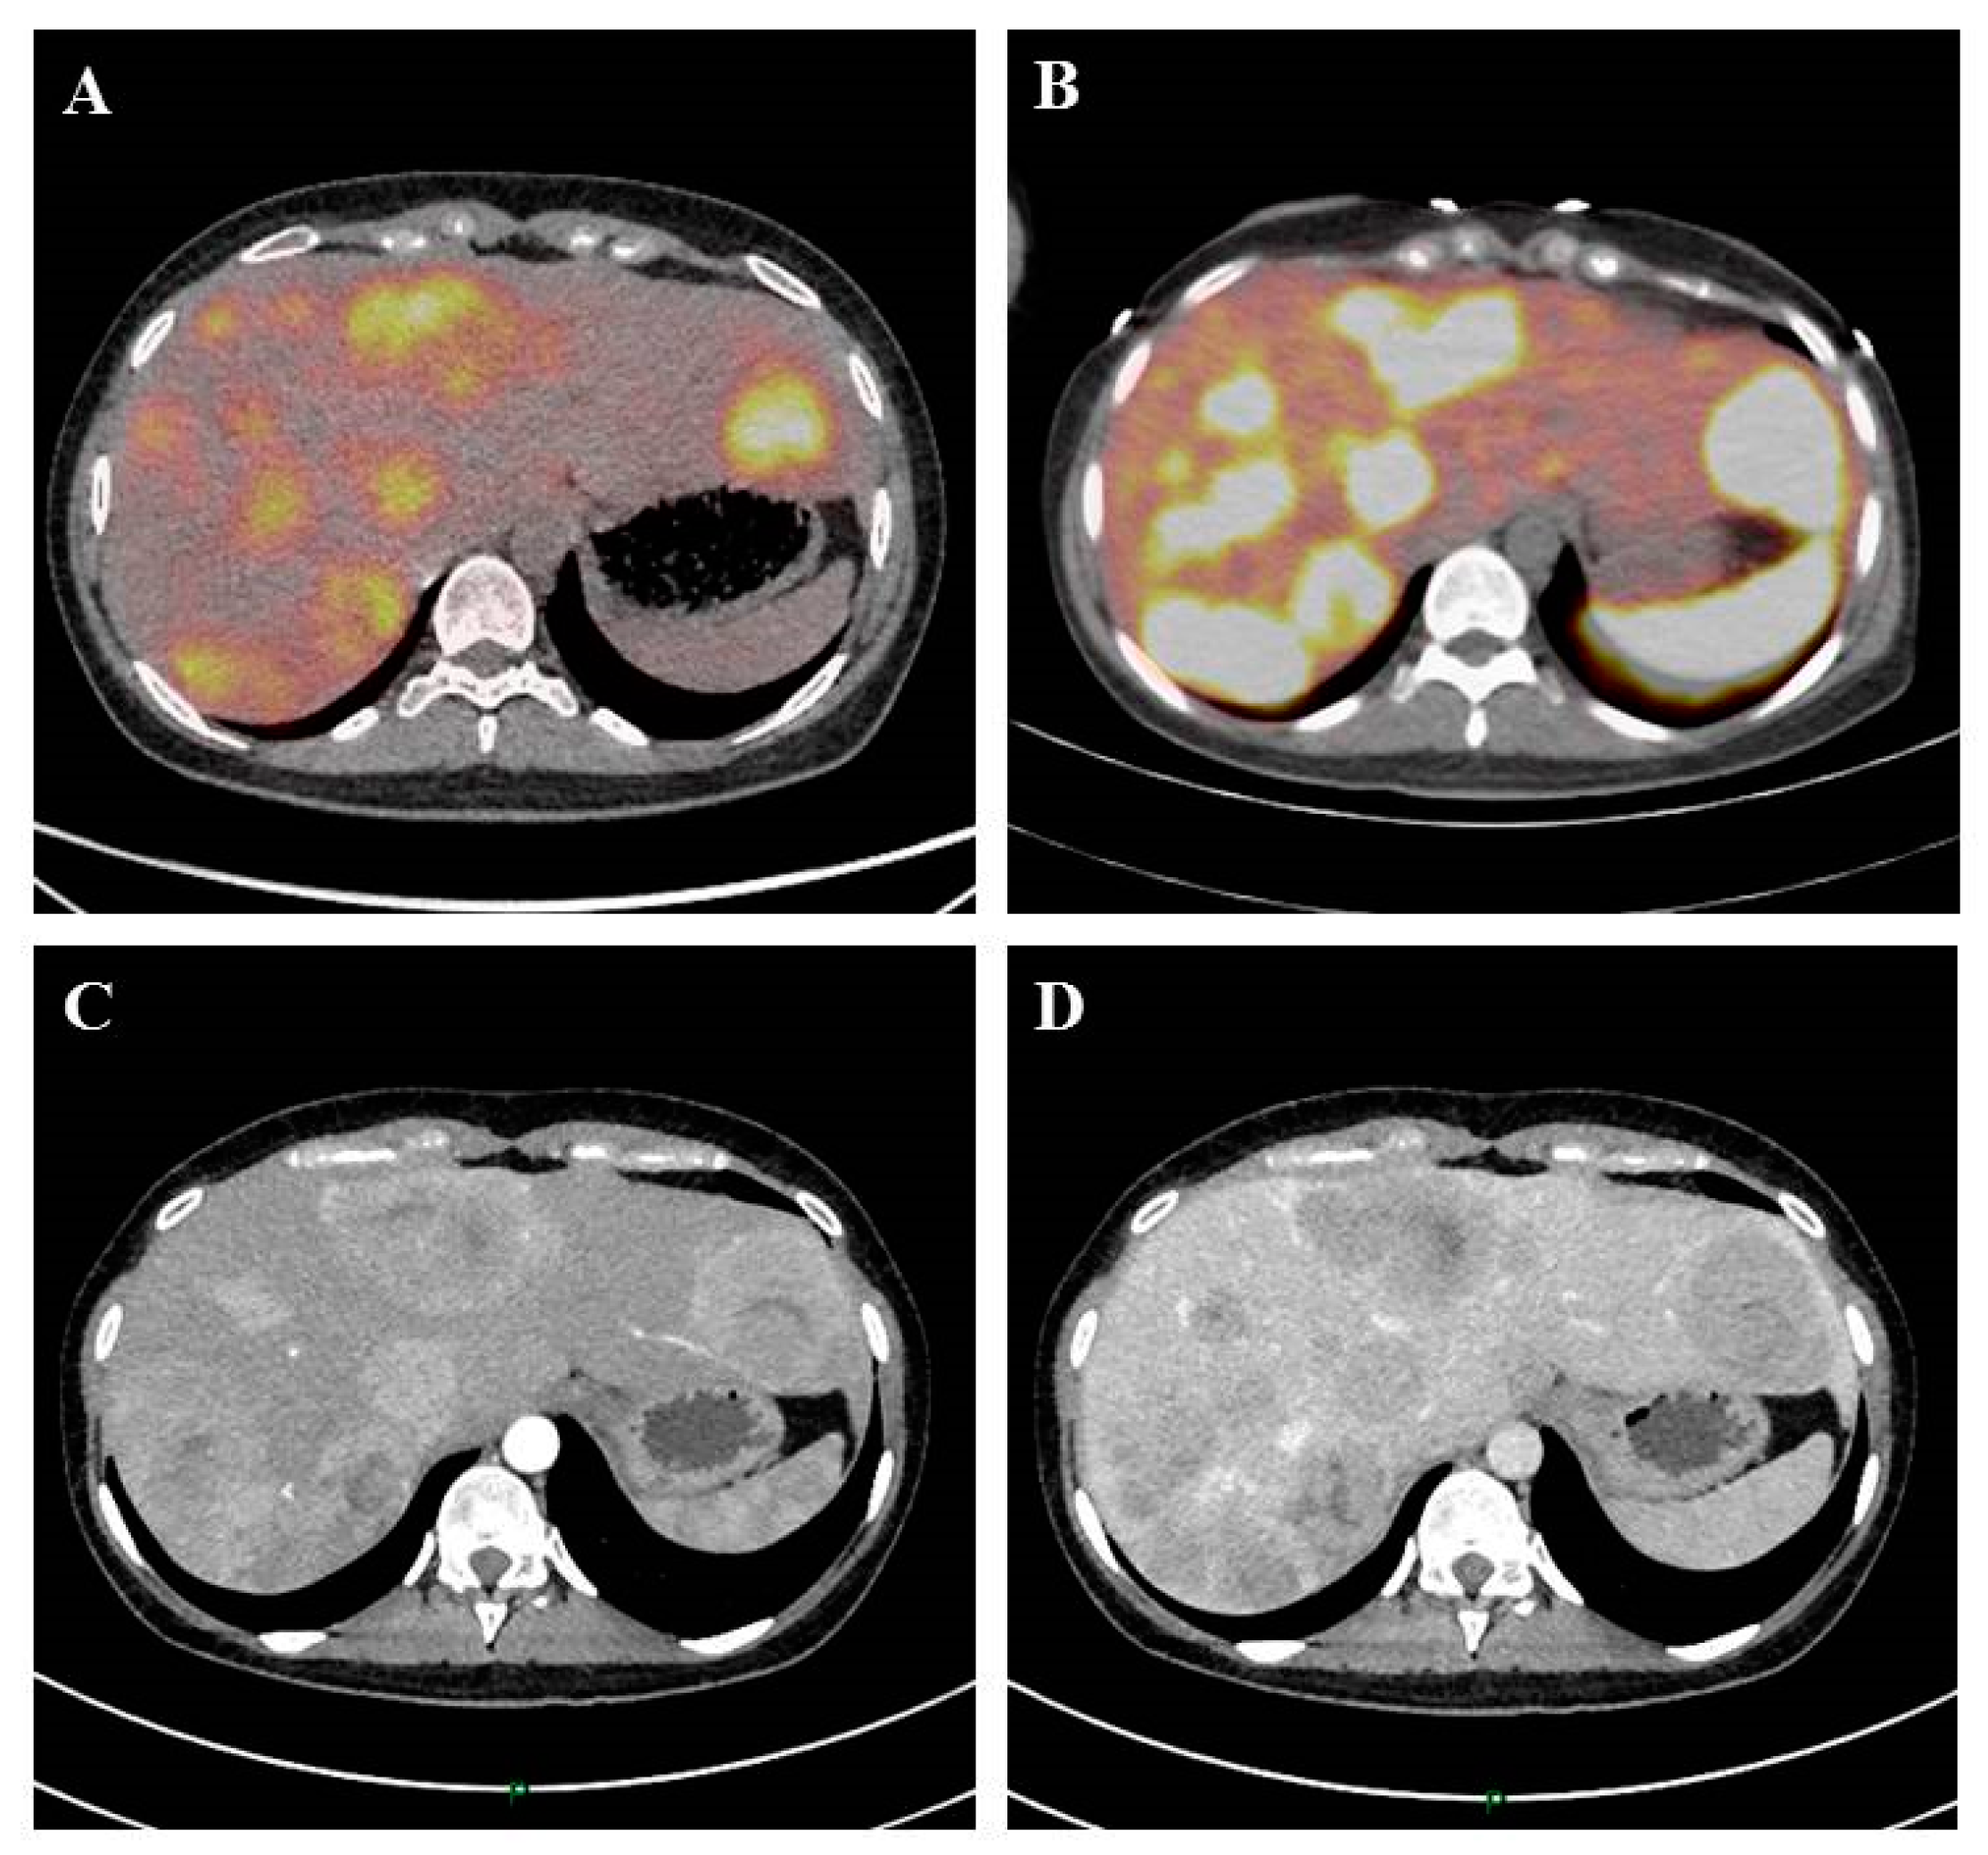

Figure 1.

A 24-year-old patient with liver metastasis of a pancreatic neuroendocrine tumor. Initial evaluation identified liver metastases on 18 F-FDG PET Computed tomography scan (A), 68Ga-DOTATOC (B), computed tomography scan at the arterial phase (C), and computed tomography scan at the venous portal phase (D).